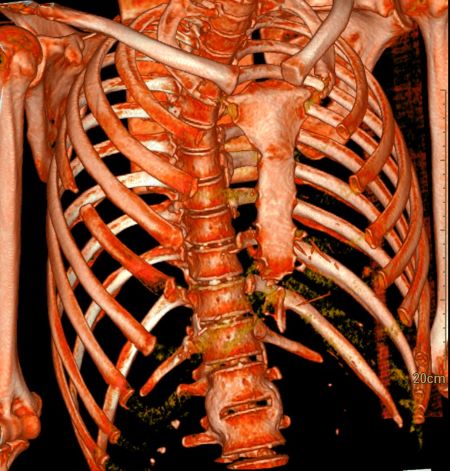

Отмечался перелом переднего отрезка 5-го ребра справа с формированием диастаза между отломками до10 мм. В окружающих мягких тканях мелкие костные структуры размером до 2 мм.Заключение

С учетом анамнеза и данных МСКТ-исследования было вынесено заключение КТ-картины полостного образования в верхушке левого лёгкого, с наличием участка консолидации, очагов отсева в верхней доле левого лёгкого, субплеврального образования в верхней доле левого лёгкого, левостороннего плеврального выпота, с признаками утолщения листков плевры, фиброзных изменений левого лёгкого, очагов по типу «дерева в почках» с формированием участка консолидации в нижней доле правого лёгкого (данные изменения, вероятно, соответствуют проявлениям вторичного туберкулёза, дифференцированного с периферическим образованием с признаками вторичных изменений. Перелом переднего отрезка 5-го ребра справа.